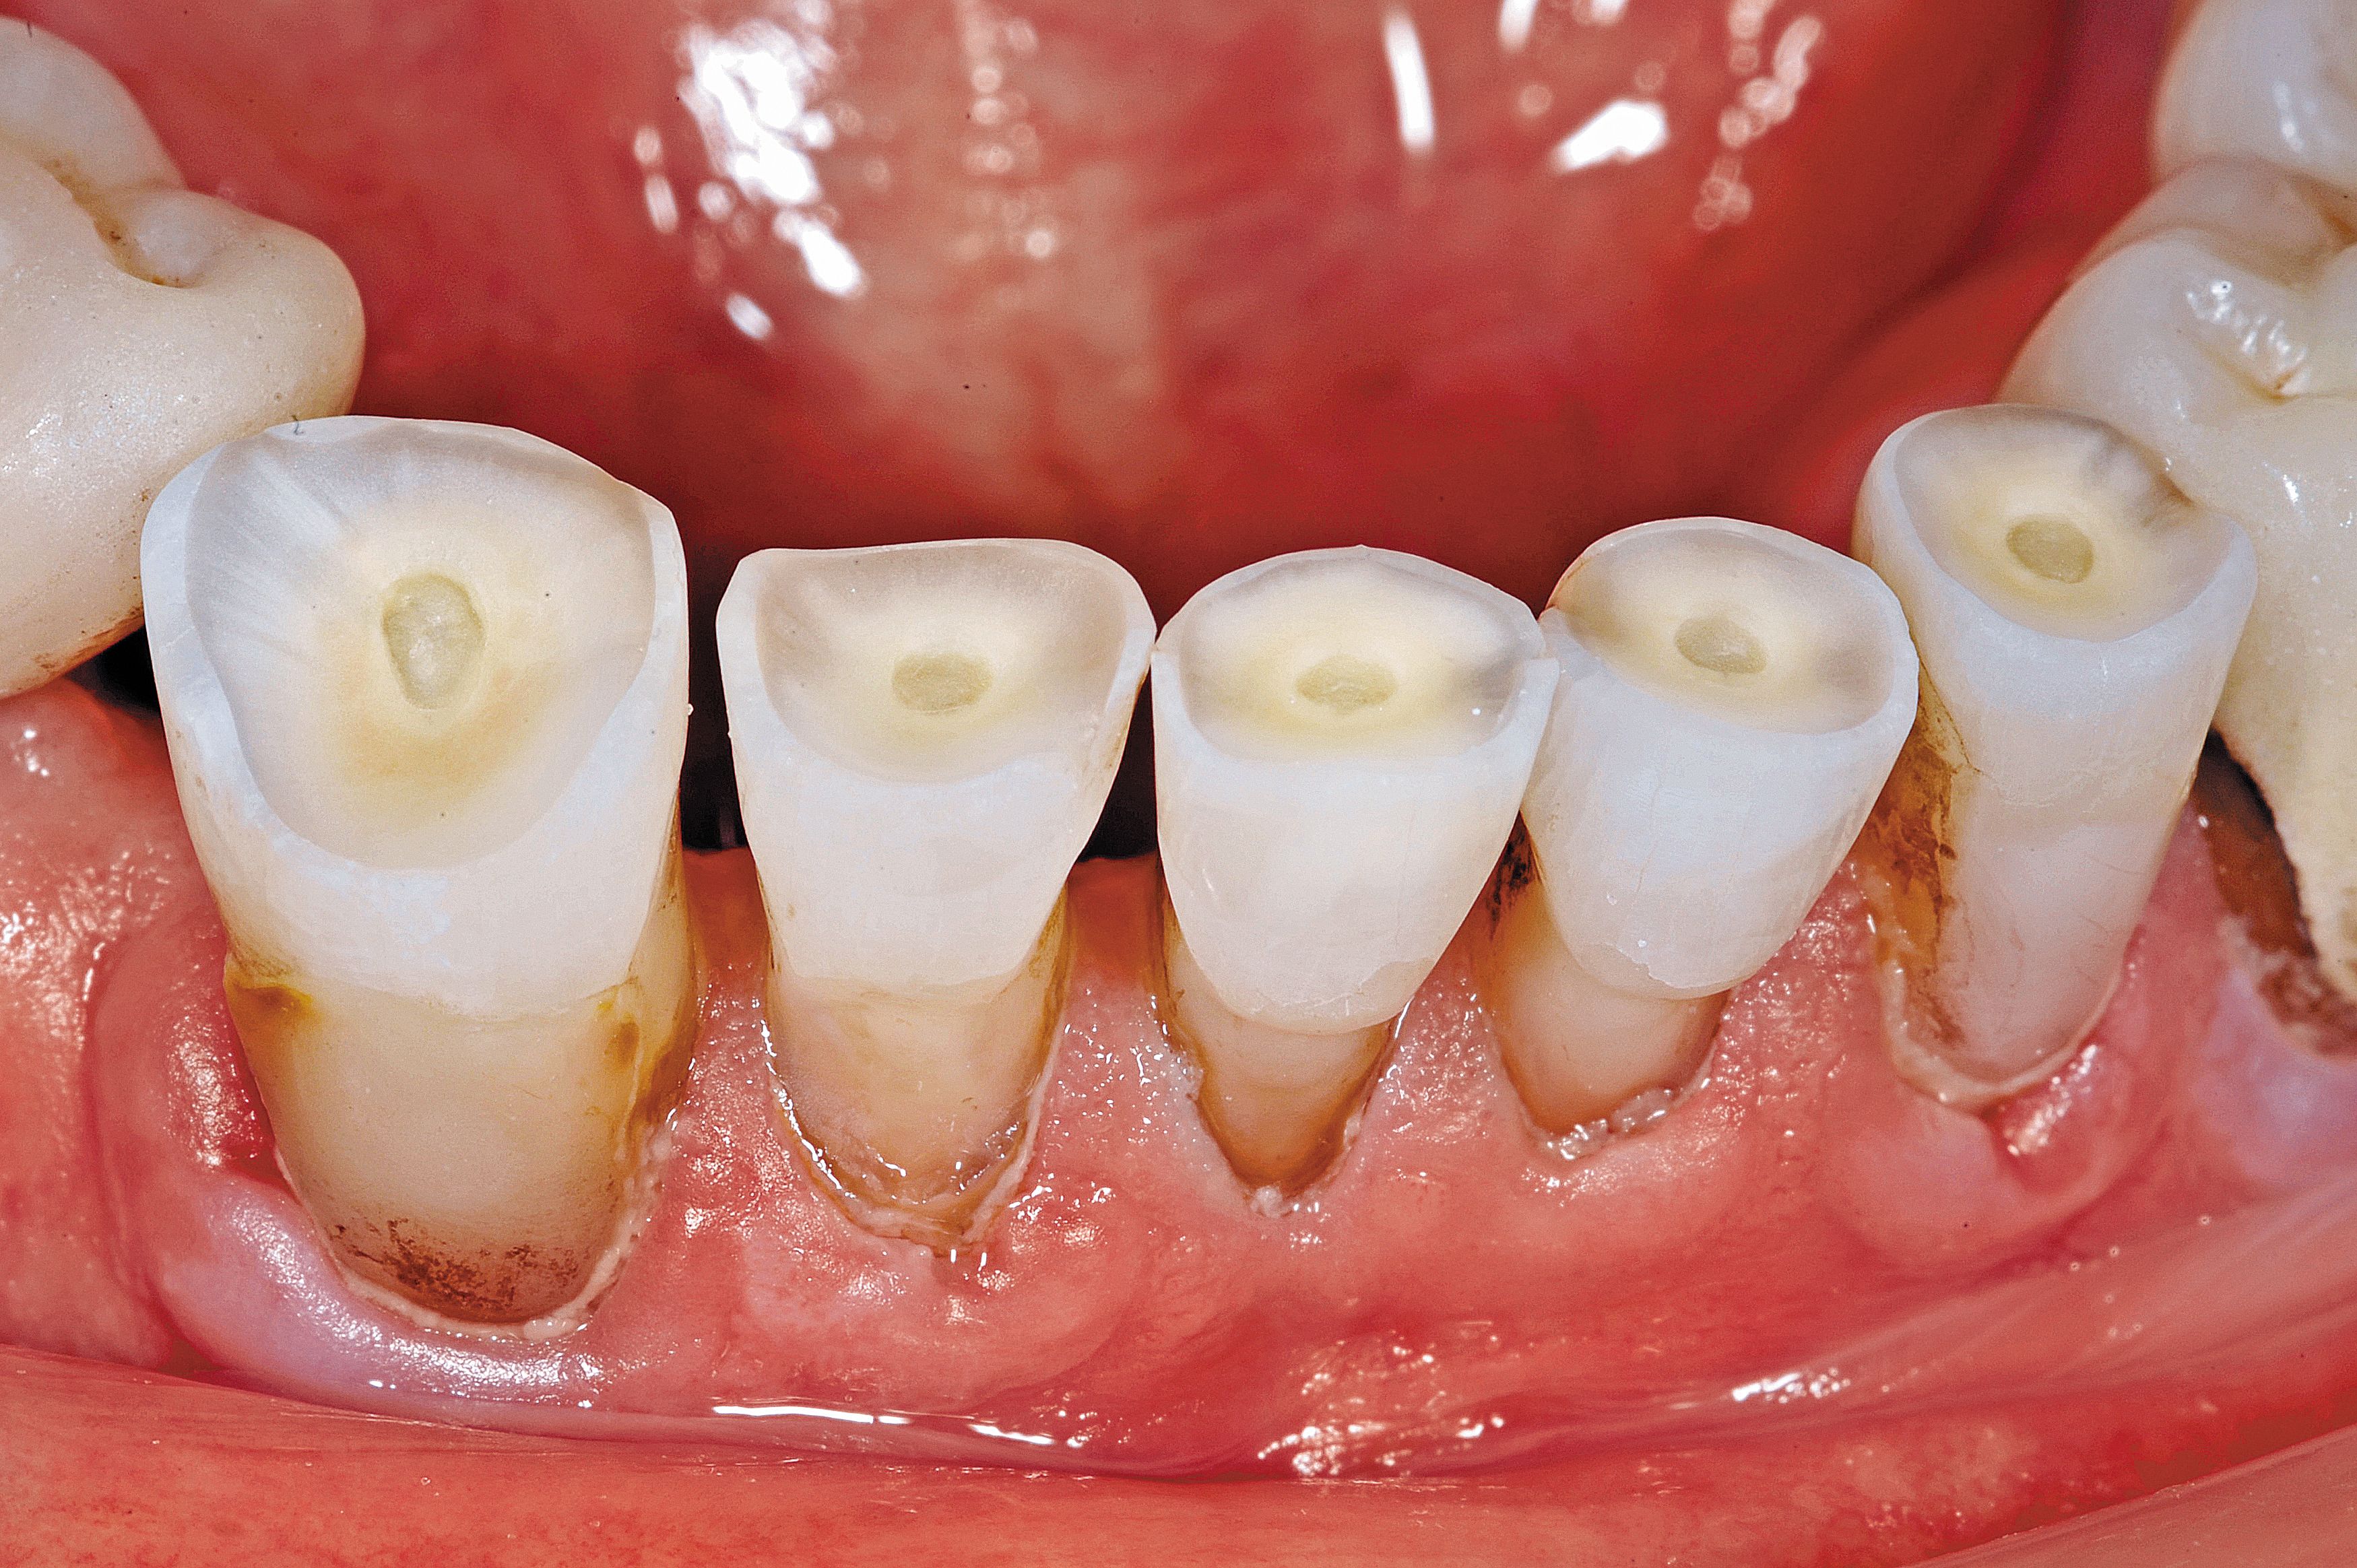

Fig. 3

Dentin and cementum surfaces that are exposed to the oral environment are not easily bonded. Contaminants such as chemicals, foods, fluoride and medications decrease the bondability of these surfaces unless they are prepared. Instead of using a bur and more aggressive dentin removal, the exposed dentin surfaces were air abraded using 50 micron aluminum oxide until frosty (Fig. 3).

A MicroEtcher (Danville Engineering) was used to clean the dentin surface, remove the outer layer and provide micromechanical retention. The goal was not to remove healthy tooth structure as would be done if retention grooves were cut with a handpiece and bur but instead to change the surface area and prepare it for more successful adhesion.